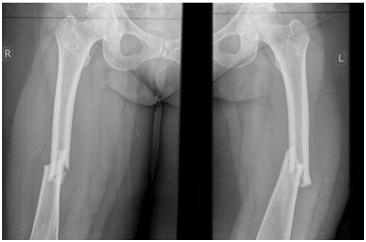

A 71 year old post menopausal Caucasian woman with elevated BMI of 34 & NIDDM, presented to the emergency department with acute severe bilateral thigh pain and inability to weight bear following a low impact fall from standing height. She also complained of an 18 month history of bilateral thigh, groin & back pain, for which she was diagnosed with “fibromyalgia”. She had been taking ibandronic acid 150mg by mouth monthly for the last 5 years for the treatment of postmenopausal osteoporosis. Plain radiographs of both limbs revealed a displaced fracture in mid-shaft region of both femori (Figure 1). Ibandronic acid was stopped and the patient underwent internal fixation with bilateral intramedullary reconstruction nails, locked proximally and distally (Figures 2 & 3). The patient made uneventful post-operative recovery and was subsequently discharged with outpatient follow-up.

Figure 1 Atypical bilateral mid-shaft femoral fractures with lateral cortical thickening.